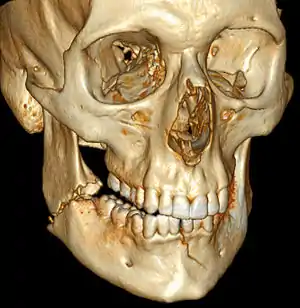

| 3D computed tomographic image of a mandible fracture in two places. One is a displaced right angle fracture and the other is a left parasymphyseal fracture. | |

Mandibular fracture, also known as fracture of the jaw, is a break through the mandibular bone. In about 60% of cases the break occurs in two places.[1] It may result in a decreased ability to fully open the mouth.[1] Often the teeth will not feel properly aligned or there may be bleeding of the gums.[1] Mandibular fractures occur most commonly among males in their 30s.[1]

Mandibular fractures are typically the result of trauma.[1] This can include a fall onto the chin or a hit from the side.[1] Rarely they may be due to osteonecrosis or tumors in the bone.[1] The most common area of fracture is at the condyle (36%), body (21%), angle (20%) and symphysis (14%).[1] While a diagnosis can occasionally be made with plain X-ray, modern CT scans are more accurate.[1]